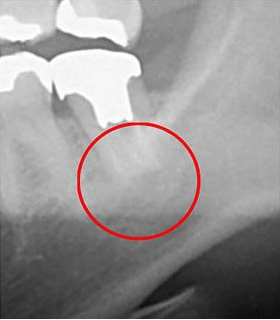

次の画像は、同じ歯をCTとレントゲンで撮影したものの比較です。

左がCTで、右がレントゲンです。

左の画像には黒い影が見えますが、右の画像には見えません。この黒い影は歯の根の炎症です。つまり、レントゲンだけではこの炎症は見逃される可能性があるのです。CTを使用することで、初期の炎症も見逃さず、適切な診断が可能になります